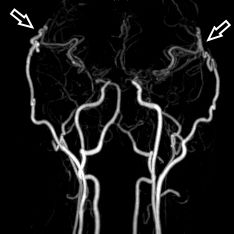

Die konventionelle cerebrale Angiographie ist die wichtigste Untersuchung zur Diagnosestellung der Moyamoya Krankheit. Diese Untersuchung ist zu vergleichen mit einer Herzkatheteruntersuchung, eben nur mit Darstellung der Hirnarterien. Bei Moyamoya-Patientinnen und Patienten werden, im Gegensatz zu Routineuntersuchungen bei anderen cerebralen Erkrankungen, selektiv die vordere und hintere Zirkulation des Gehirns dargestellt, sowie auch die Versorgung der extrakranialen Gefäße. Diese umfassende Darstellung ist besonders wichtig, um die vollständige Ausdehnung der Erkrankung zu erfassen und alle möglicherweise veränderten Blutflüsse im Gehirn zu verstehen. Je nach Befund werden die Engstellen der Hirnarterien, sowie auch mögliche begleitende Veränderungen selektiv hochauflösend dreidimensional dargestellt. Es ist wichtig zu erwähnen, dass die Moyamoya Krankheit nicht über eine Katheterintervention (Ballonaufweitung der Engstelle) behandelt werden kann und darf. Dies haben mehrere Studien gezeigt.

Angiographie beidseitige Moyamoya Krankheit

Konventionelle Angiographie eines Patienten mit beidseitiger Moyamoya Krankheit (links). 3-dimensionale Darstellung eines Aneurysmas einer jahrelang stark beanspruchten Spontan-Kollaterale (rechts).

3D MRT Darstellung

1 Jahr postoperativ: 3D MRT Darstellung der extrakraniellen-intrakraniellen Bypässe (Pfeile)